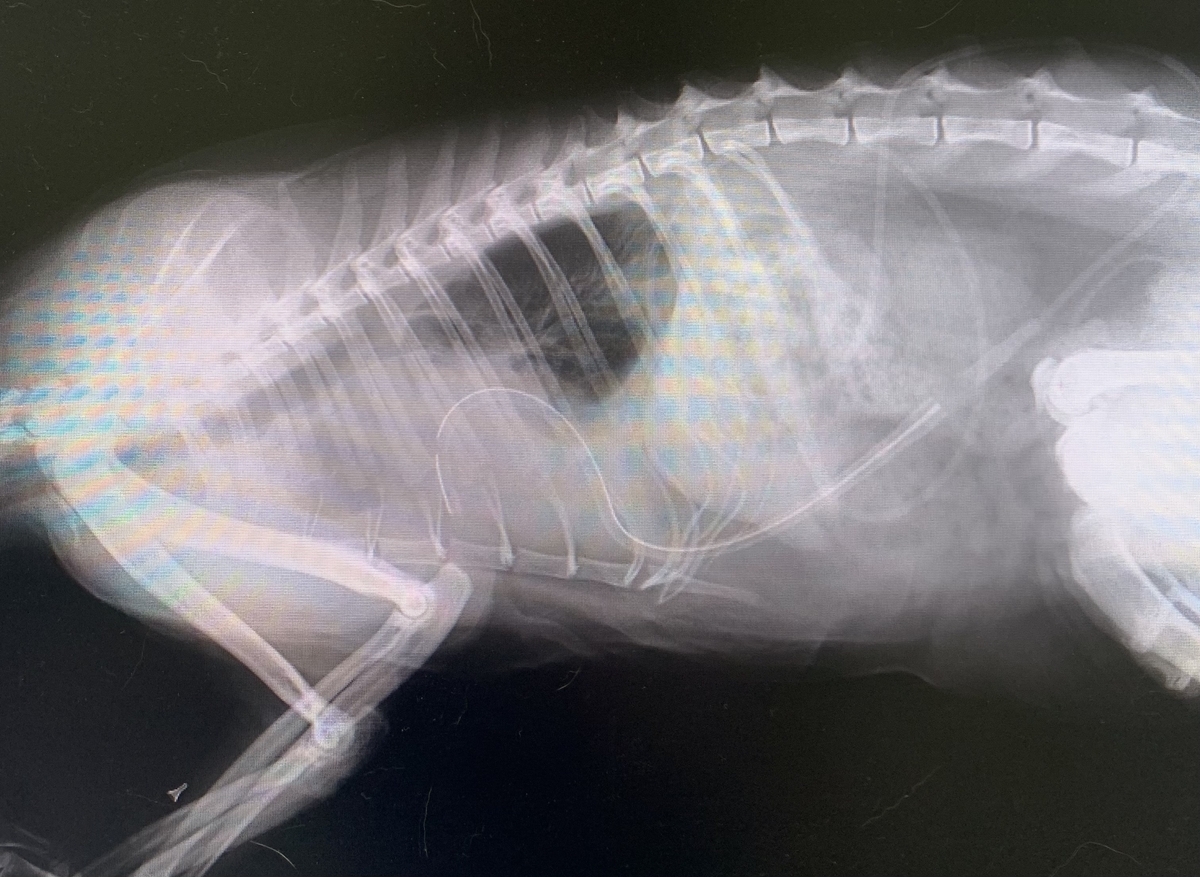

X線やエコー検査にて胸水貯留、前縦隔内の充実物がみられました。胸水は乳びで、CT検査にて突発性乳び胸と診断されました。

初期治療で胸水抜去で通院していましたが、胸水の貯留と肺の繊維化に伴う萎縮が進行し、胸水の貯留する期間がどんどん短くなっていました。オーナー様も通院が難しく、また猫ちゃんの通院ストレスもかなりあった為、胸腔ドレーンを設置しました。

この症例は術後1ヶ月ほどで胸水が抜去できないくらい少なくなったため、ドレーンを抜去しました。